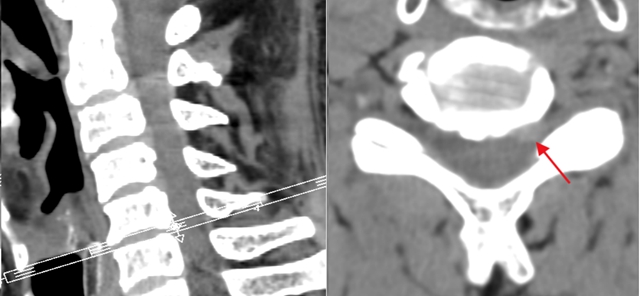

男子手麻!竟是這兒出問題

近日,西南醫(yī)科大學附屬中醫(yī)醫(yī)院骨傷科脊柱·腫瘤一組通過頸椎椎間孔鏡微創(chuàng)手術,為一位70歲因頸椎間盤突出導致左上肢劇烈疼痛、麻木的患者解除病痛。術后,患者癥狀明顯緩解。病例回顧:1周手臂疼痛,讓他“徹夜難眠”  “晚上疼得睡不著覺?!薄 ?...